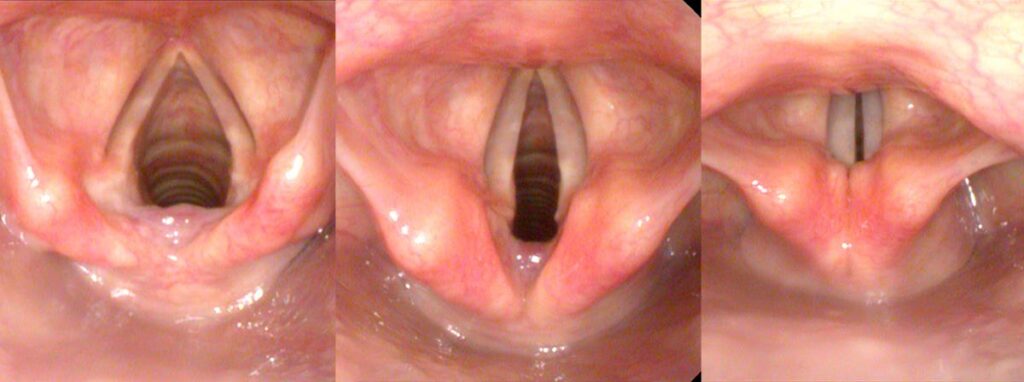

For hoarseness, we are generally interested in the vocal cords, located posterior to the thyroid cartilage. The vocal cords can easily be visualized from above, by passing a device into the pharynx. A rigid endoscope views the larynx from the back of the mouth. A flexible endoscope views the larynx from the back of the nose.

The front of the thyroid cartilage is triangular or tent-like in shape, suspending and protecting the vocal cords, with the Adam’s apple representing the apex. Inside, the airway is essentially a round tube with the vocal cords narrowing the airway, acting as a valve — technically, the glottis. The vocal cords narrow the opening to a triangle. During exhaling (breathing out), the vocal cords narrow the triangle to keep some back pressure in the lungs. During phonation, the vocal cords come almost completely together to form a narrow slit. Air passing between the vocal cords sets them vibrating and generates sound.